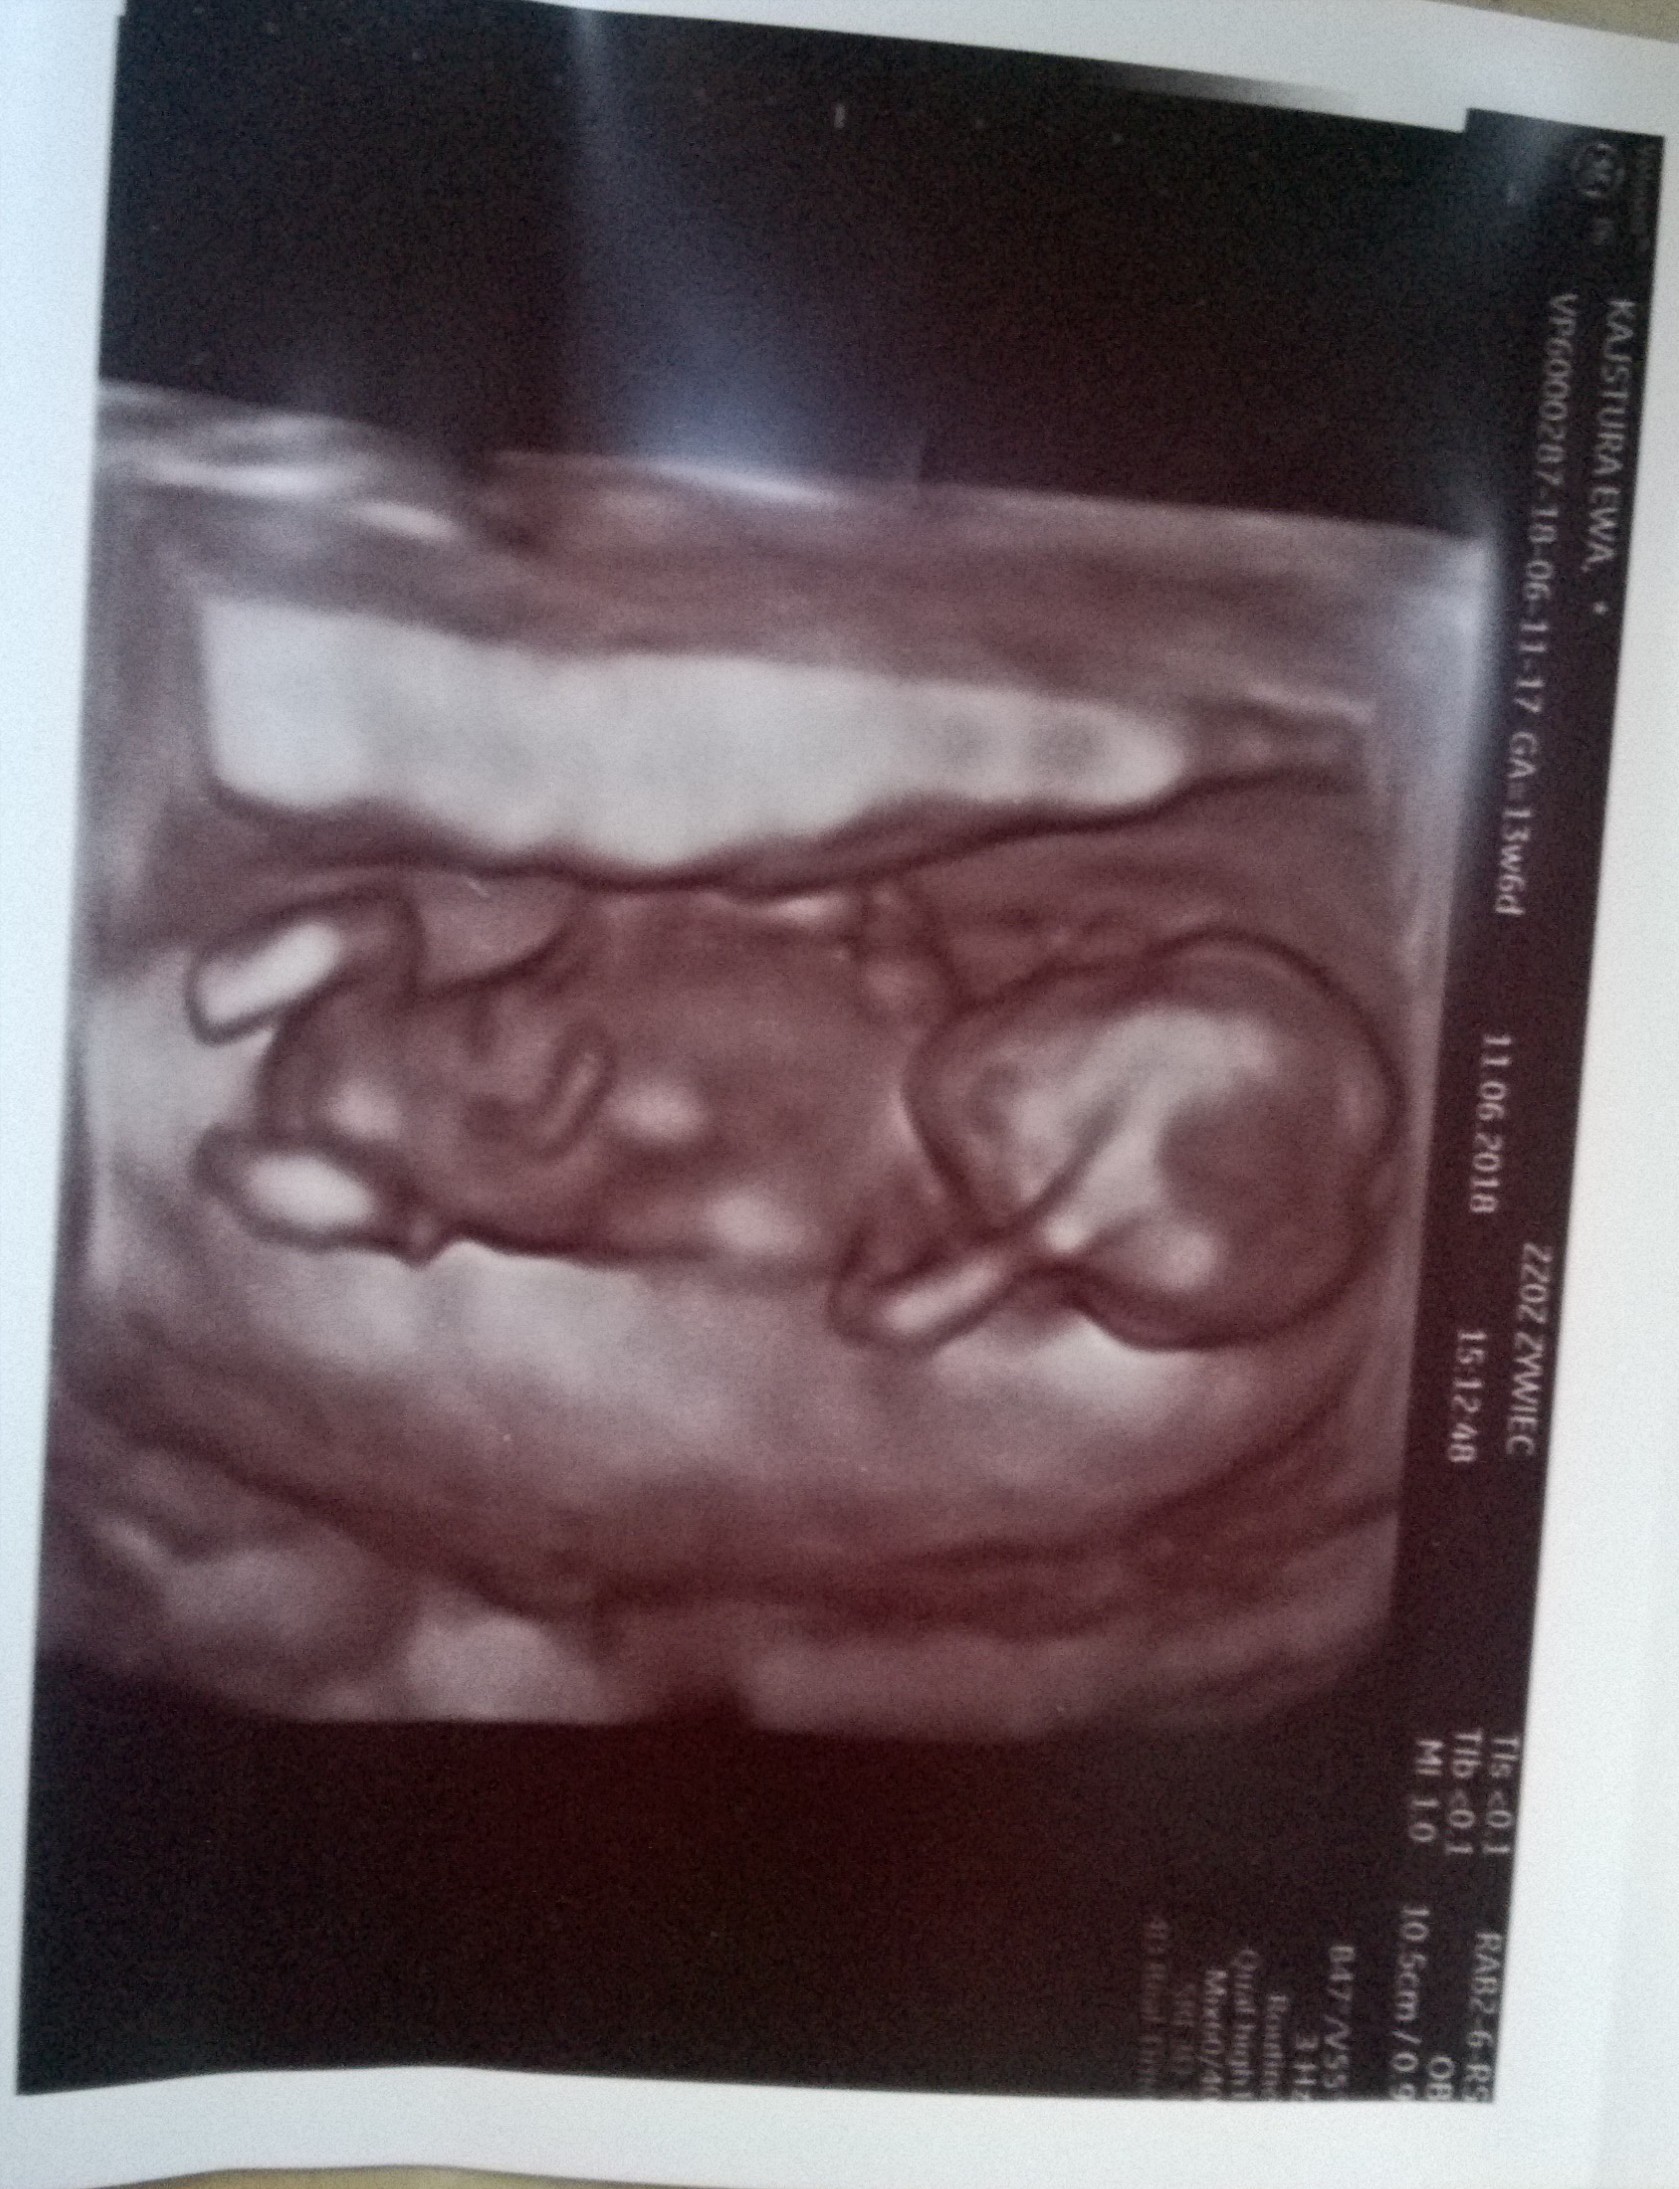

Dziś jest początek 14 tygodnia, wg usg jest 13t4d. Szczerze to nie wiem ile dzidziol ma cm, nie skupiłam się na tym, stresu miałam z tą przeziernoscia, a lekarka nie dała mi żadnego potwierdzenia z badania, tylko info że wyniki będą na wizycie, która za 3 tygodnie.Dzieki dziewczyny- w takim razie nie będę sie przejmować kierowniczka, moze sama niedoinformowana jest. Najwyżej za dwa tygodnie u lekarza zapytam o takie zaświadczenie.

Shiran który masz tydzien i jakiej wielkości jest dzidzius? Ja teraz w 13t6d mialam przyziernosc 1,3, dzidzi cos ponad 7cm (niestety nie dopatrzyłam dokladnie a na zdjęciu nie mam tego pomiaru) i lekarz mowil ze jest dobrze, ze przyziernosc powinna byc do 2mm. Według mnie możesz byc spokojna. A kość nosowa tylko lekarz ogladal i stwierdził ze prawidłowa.

Tak w ogóle moj dzidziuś z ostatniej wizyty

Zobacz załącznik 866857 Zobacz załącznik 866858 Zobacz załącznik 866859